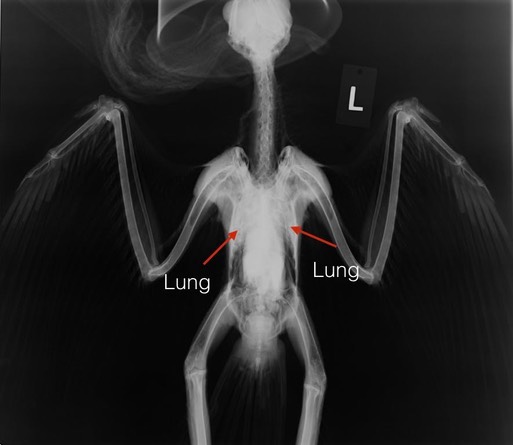

Red-tailed Hawk 18-323

A young Red-tailed Hawk was found on the ground near Yakima. It was emaciated, but had no apparent injuries. A radiograph showed the lungs looked abnormal. We suspected aspergillosis, a fungal infection that stressed Red-tailed Hawks are susceptible to. The stressor in this case may well have been starvation. The young hawk died two days after admission. A necropsy showed large numbers of fungal lesions throughout the hawks internal organs.